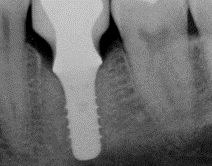

Fig 5. View of a radiograph taken of an implant in September 2009.

Figure 5

Fig 6. To demonstrate how rapidly peri-implantitis bone loss occurs, a radiograph of the same implant shown in Fig 5 taken 3 years later (left) shows significant bone loss, and the photograph (right) shows soft-tissue loss.

Figure 6